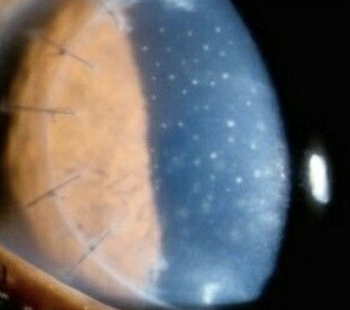

Endothelium/descemet dystrophy

Fuchs endothelial dystrophy: inc in post lamina production causing guttata on BM of endo. This results in dec endo cell (<500 cells/mm2) resulting in stomal edema. Female over 60

Symptoms. blurred/hazy vision. Early signs are glare/light sensitivity. Late signs: pain/edema

Objective: Guttata starting 20-30s, early cataract, inc irsk for POAG, >600 pachymetry. May have bullae or RCE

Plan: Hypertonic 5% NaFl drops and ung at night. Bandage SCL if bullae or RCE.